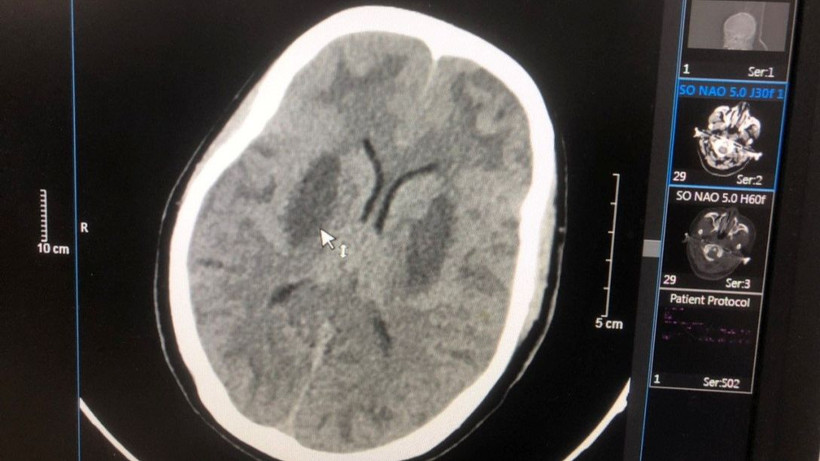

Hình ảnh tổn thương não của bệnh nhân Triệu Văn N.

Bệnh nhân nặng thứ hai là Triệu Văn N., 17 tuổi (nam), dân tộc Dao, quê Cao Bằng, vào viện ngày 24/2. Bốn ngày trước khi vào viện, bệnh nhân thấy khó thở, mệt, mờ mắt, lơ mơ, hôn mê, ngừng thở. Bệnh nhân được đưa đến Bệnh viện Đa khoa tỉnh Bắc Ninh cấp cứu.

Sau đó, bệnh nhân được chuyển tới Trung tâm Chống độc, Bệnh viện Bạch Mai trong tình trạng hôn mê, tụt huyết áp, nhiễm toan chuyển hóa nặng, tổn thương não nặng hai bên, nồng độ methanol trong máu là 125 mg/dL, không có ethanol.

Bệnh nhân đã được cấp cứu điều trị hồi sức giải độc lọc máu, hiện tri giác có cải thiện nhưng não vẫn tổn thương và phù não nhiều, tổn thương mắt.